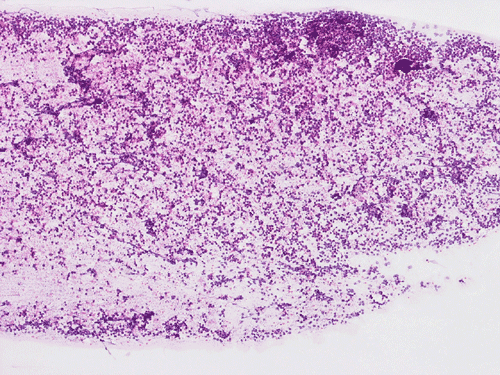

Permanent Sections:

The material for permanent sections is largely semi-liquid in consistency. There are only very few fragments of cerebellar tissue that are infiltrated by the tumor. The bulk of the diagnostic material are solid sheets of neoplastic cells (Panel G). The cytologic features are similar to what we have observed in the cytologic preparation  (Panel H). In essence, the tumor is composed of solid sheets of large polygonal and rather monotonous atypical cells with a thin rim of cytoplasm and molding which lead to a mosaic pattern. These features are consistent with lymphoma. On immunohistochemistry, practically all the neoplastic cells are positive for leukocyte common antigen (LCA) (Panel I), CD20 (Panel J) and many of them are positive for CD79a (Panel K). Only reactive T-cells but not the large, atypical cells are positive for CD3 (Panel L). The neoplastic cells are essentially negative for Bcl-6 (Panel M) but some of them are positive for Bcl-2 (Panel N). The large atypical cells are negative for kappa and lambda light chains on immunohistochemistry. There is no immunoreactivity in the neoplastic cells for cytokeratin (AE1/AE3), S100, pan-melanoma marker (Mart-1, tryptase, and HMB-45).